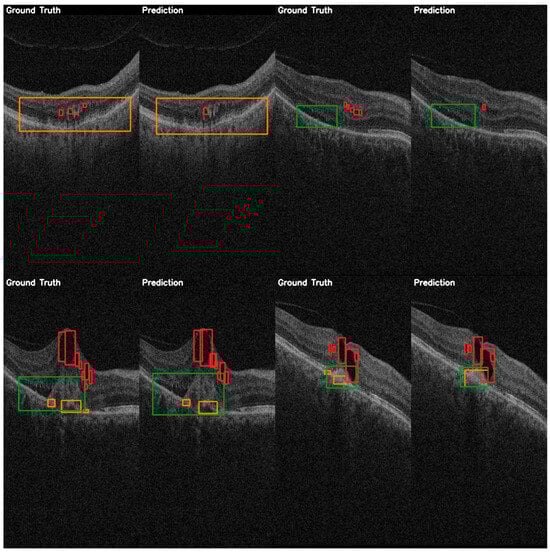

3.2. Performance Analysis of YOLO Versions on the OCT5k Dataset